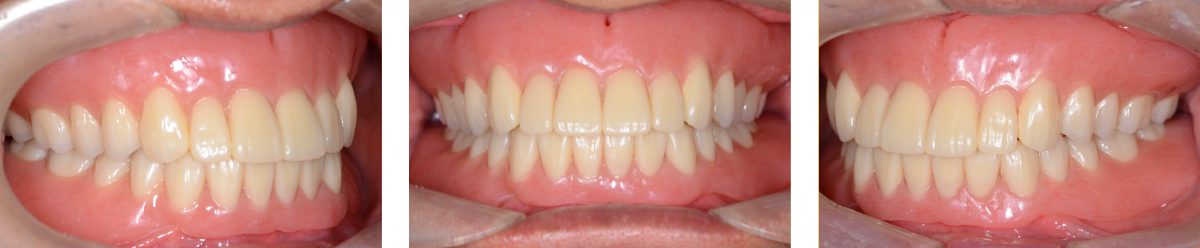

治療用義歯装着

1年6ヶ月後の口腔内

最終義歯の人工歯排列

最終義歯装着時の口腔内写真